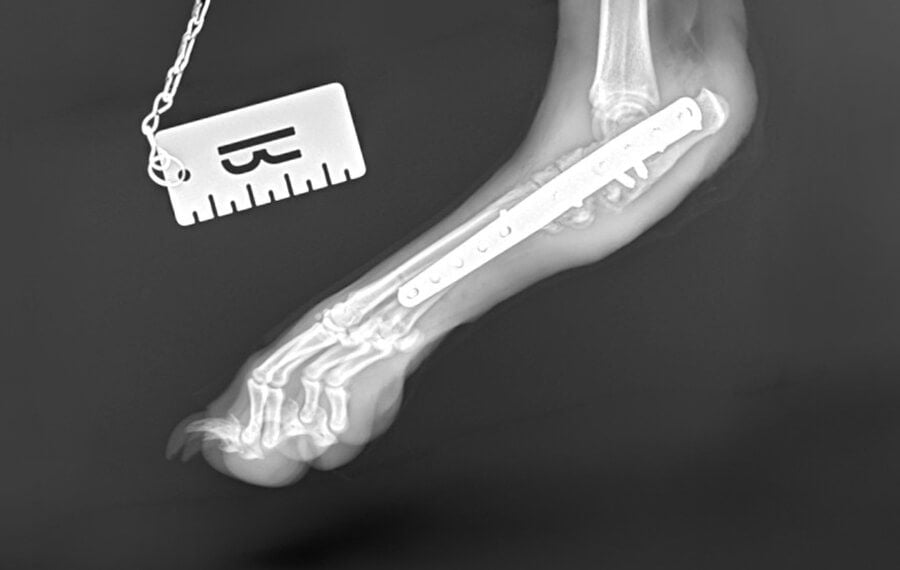

Intertarsal Arthrodesis (partial fusion of the ankle)

This is the complete fusion of the tarsus, or hock (the joint between the paw and the knee).

- Appearance: This procedure has a more obvious effect on a pet's gait compared to the front limb. Because the hock is vital for "spring," the pet may have a slightly stiffer step. However, dogs and cats still regain very good mobility and are typically able to run and play happily after surgery.

- Common Indications: Performed for pets with severe hock arthritis or catastrophic injuries, such as Achilles tendon ruptures or severe ligament instability.